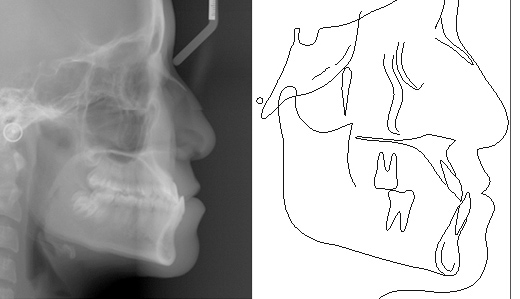

口腔CT图